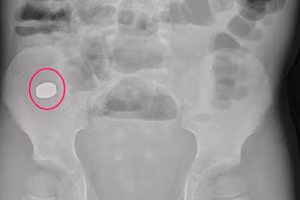

GD&TĐ - Ngày 30/9, tin từ Bệnh viện Đa khoa Trung ương Cần Thơ, các bác sĩ vừa lấy dị vật là hạt hồng xiêm bị bỏ quên nhiều năm trong người bệnh nhân.